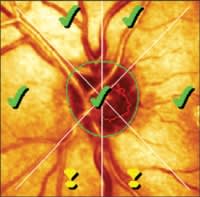

Two views of the HRT Moorfields Regression Analysis results are shown above. Borderline rim thinning in the inferior and inferior temporal regions correspond with the superior visual field defect.